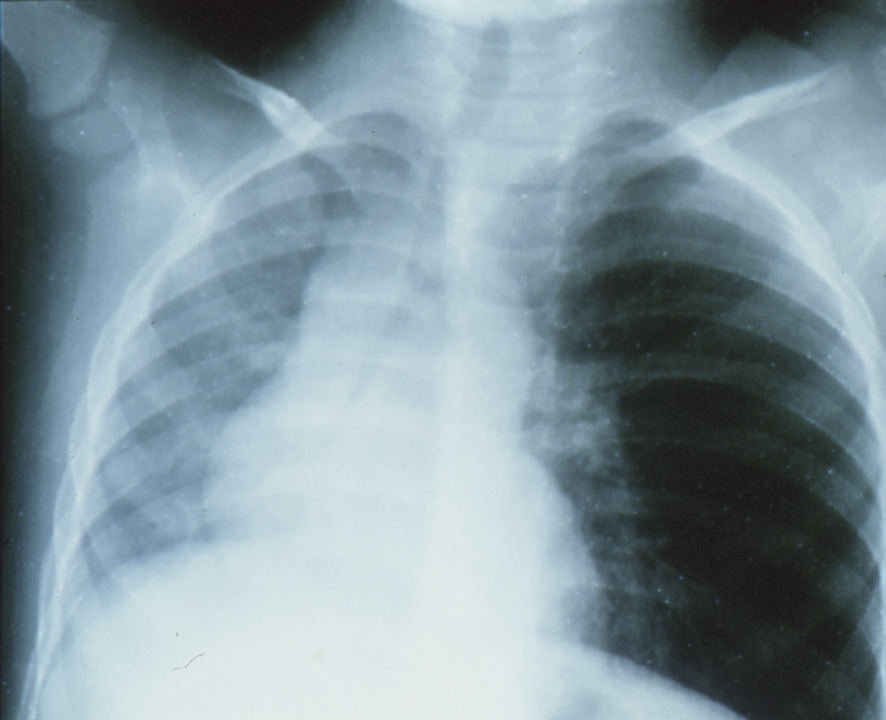

Si l’enfant après une période de toux brutale et de gêne respiratoire (syndrome de pénétration) respire à nouveau normalement, il faut néanmoins qu’il soit examiné : auscultation pulmonaire et radiographies du thorax en expiration et en inspiration (fig. 2 ).

En cas d’anomalie, une fibroscopie laryngotrachéale est réalisée en urgence, sous anesthésie locale, suivie, en cas de visualisation de corps étranger, d’une bronchoscopie.5

Des examens normaux n’éliminent pas formellement une localisation bronchique, qui peut causer une pneumopathie et éventuellement une dilatation des bronches. Ainsi, lorsque les parents décrivent un syndrome de pénétration, il faut faire une fibroscopie (sans urgence), chez un enfant à jeun. L’extraction est réalisée sous anesthésie générale.

Si l’enfant après une période de toux brutale et de gêne respiratoire (syndrome de pénétration) respire à nouveau normalement, il faut néanmoins qu’il soit examiné : auscultation pulmonaire et radiographies du thorax en expiration et en inspiration (